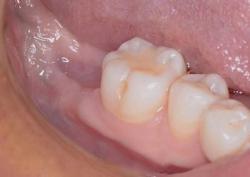

Метод выбирают по рентгеновскому снимку и осмотру. Врач учитывает форму корней, объем разрушения, состояние кости и мягких тканей. В практике применяются:

В зависимости от ситуации выполняют простое или сложное удаление. При сложном варианте зуб могут разделить на части, чтобы убрать его аккуратно и без лишней травмы.

Лунку очищают, при необходимости проводят обработку антисептиком, ставят гемостатический материал, иногда накладывают швы.

Результат:

болевой синдром и отёк купированы, заживление прошло без осложнений, соседние зубы и костная ткань сохранены.